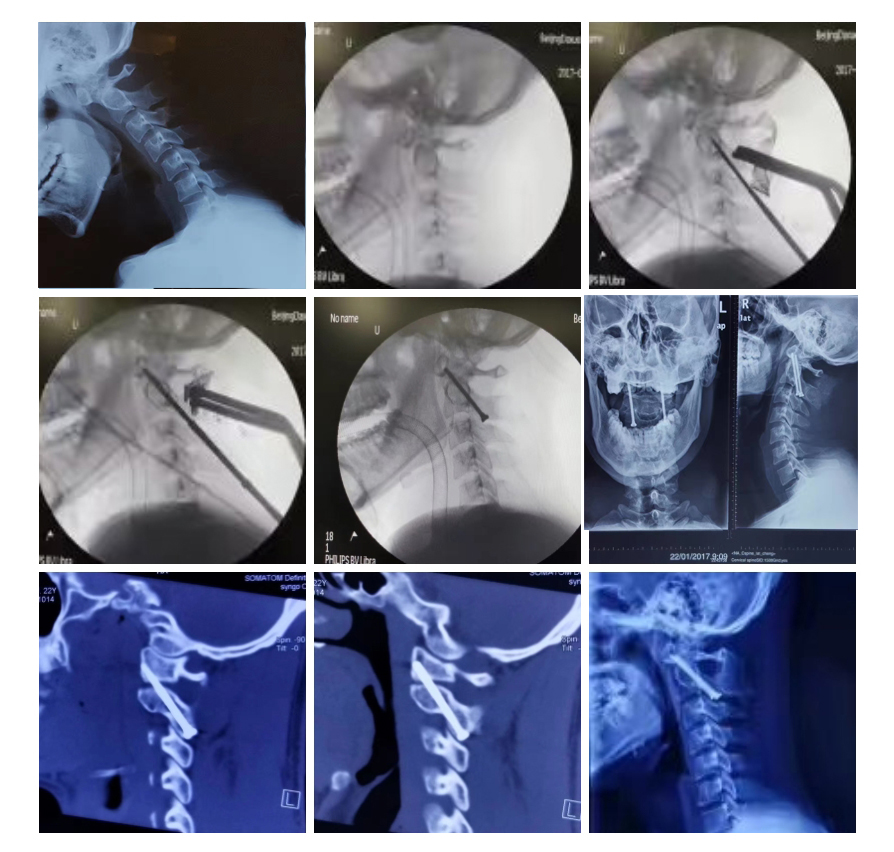

典型病例三:经典“改良Magerl术”

22岁男性,齿突不连,寰枢关节不稳定。2年前行后路改良Magerl 术(经枢椎椎弓根寰椎侧块螺钉固定寰枢后弓颗粒状松质骨植骨融合术)。图6为术后3天影像。图9为最近复查影像。

典型病例四:经典“经口松解复位+后路枕枢固定植骨融合术”

这是10年前的一个病例,男性18岁,寰椎枕化畸形,寰枢关节脱位,颈髓空洞,小脑扁桃体疝。做了经口松解复位、后路枕枢固定植骨融合术。图4为术后五天的核磁影像。图5为术后五个月的CT,植骨融合成功。图6为术后五个月的核磁,见空洞闭合了,小脑扁桃体也回位了。